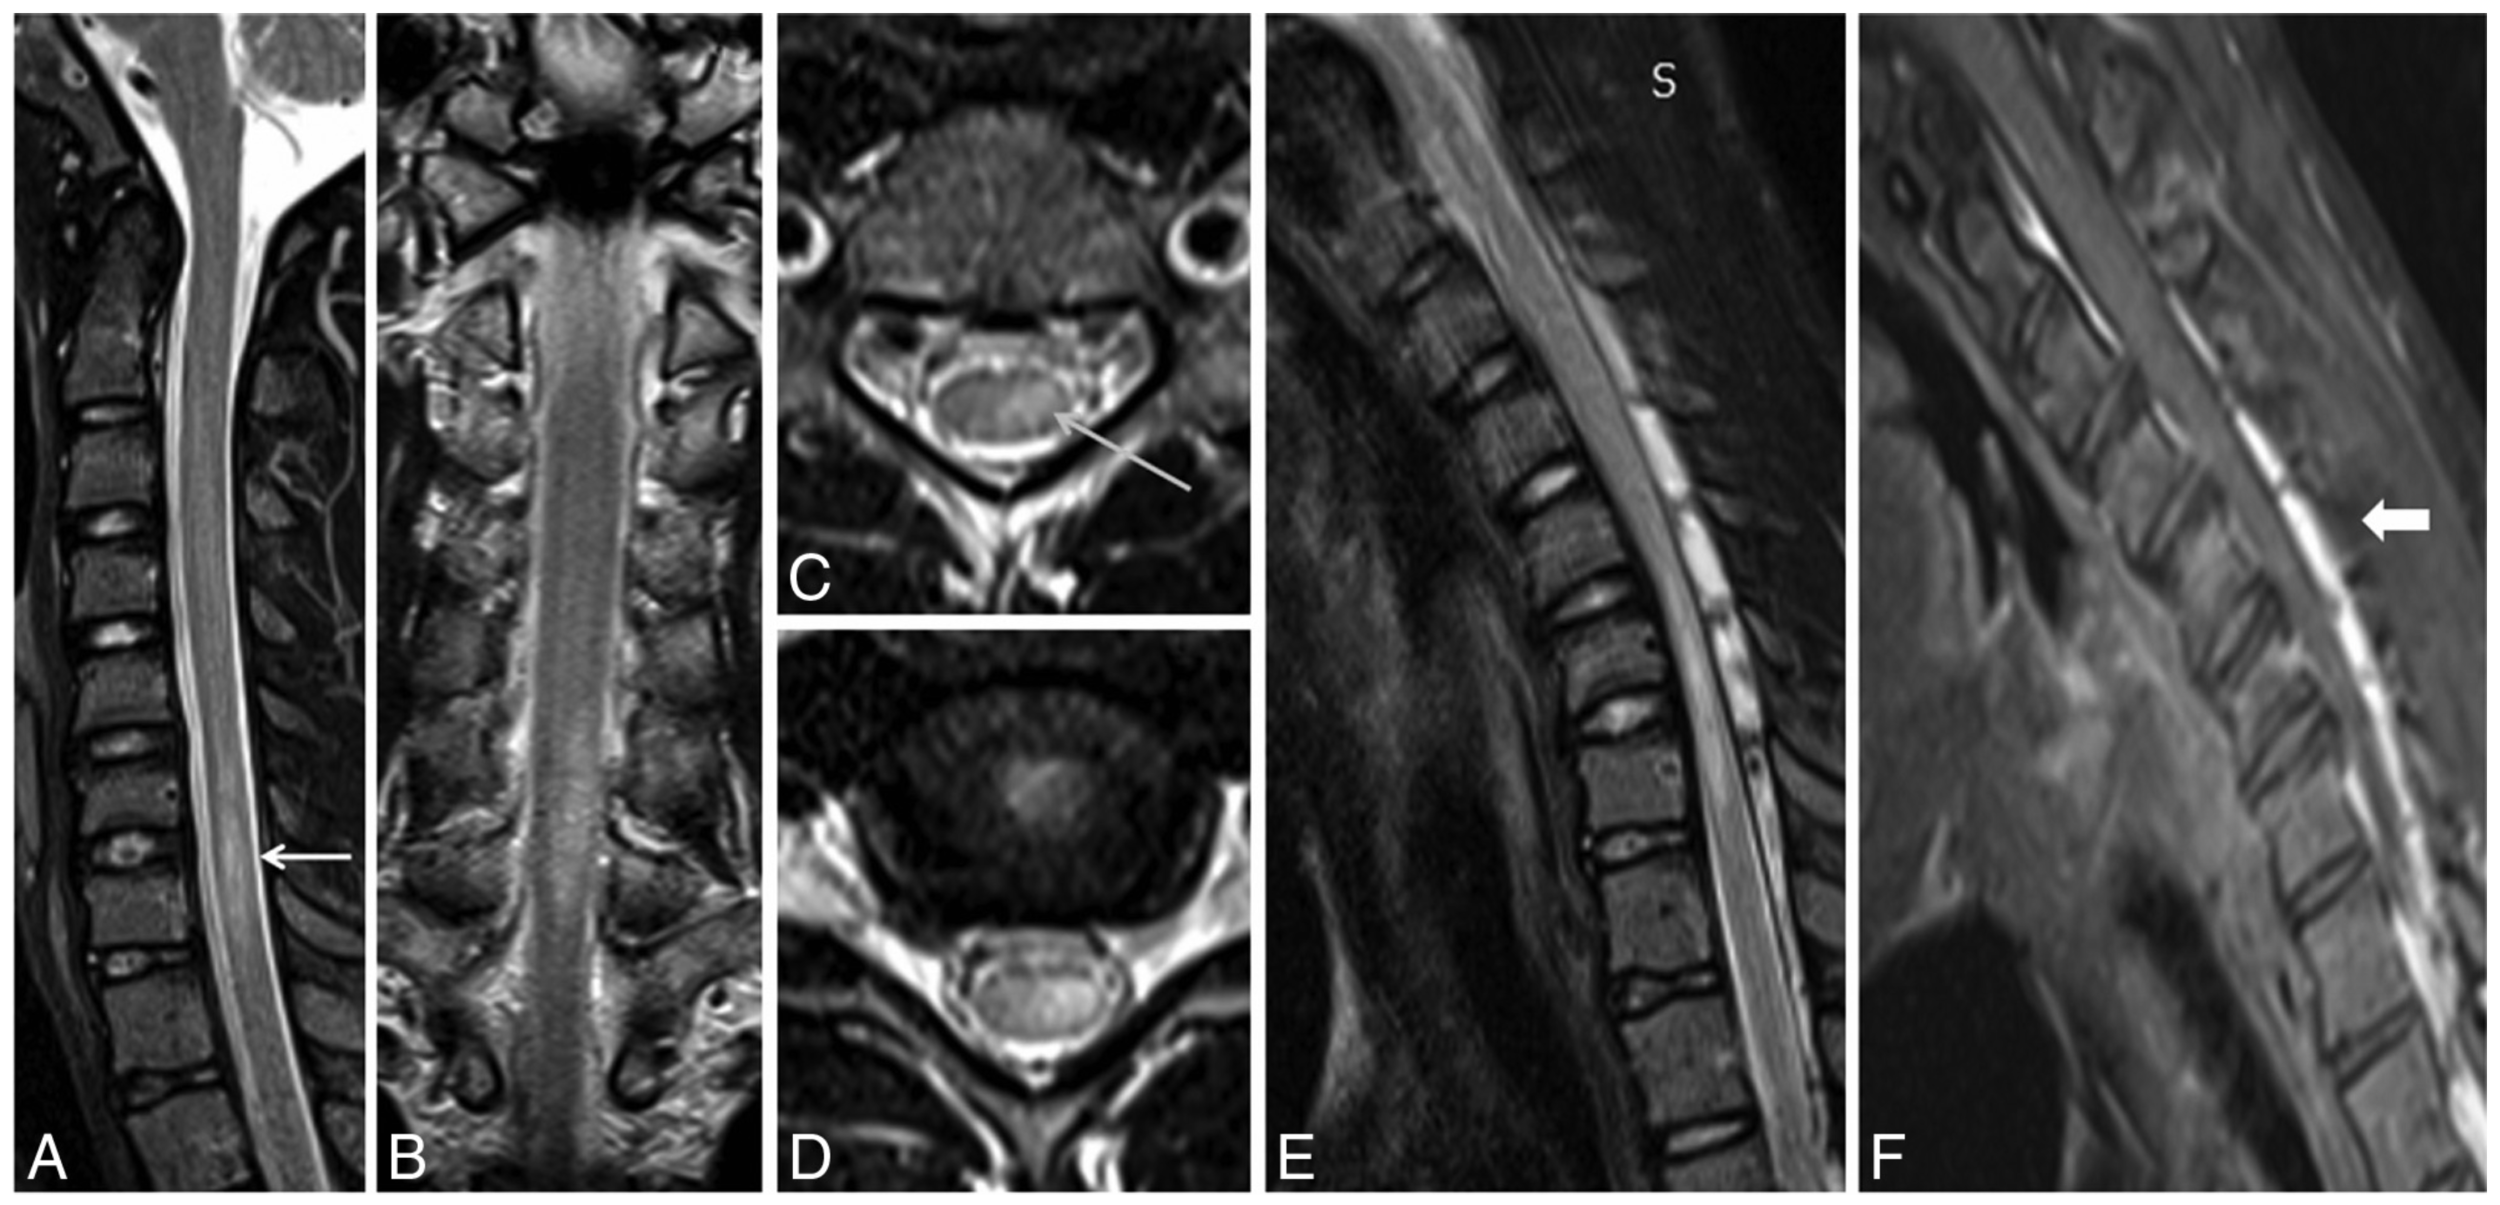

Imaging findings

fig. 3

- Loss of dural attachment, forward shifting of posterior dura, enhancing prominent posterior epidural space: 100%

Results

fig 1

fig 2

- Max LDS: 3 - 10mm, mean 6mm

- Posterior epidural flow voids: 47%

- Most had increased LDS at both C & T spine

- Diameter of bony canal not sig changed

- At max compression site, cord flattened in AP dimension by avg of 0.7mm

- Mean decrease in AP/TR ratio of 0.12